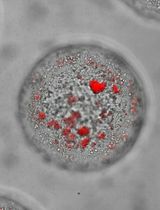

Figure 2. Representative images of the (A, D) thin film, (B, E) hydrated thin film, and (C, F) DLS volume distribution. The top panel represents drug-incorporated micelles prepared using optimal conditions, as demonstrated by the monodisperse volume distribution with a single peak around 27 nm. The bottom panel is representative of sub-optimal conditions, indicated by the cloudy thin film and the incomplete hydration of the thin film, resulting in polydisperse size distribution with a peak at about 105 nm and a large peak of aggregates in the micrometer range.

Note: The DLS data were obtained from a separate experiment and do not represent the size distribution of the micelles shown in the images and is used here for demonstration purpose only.